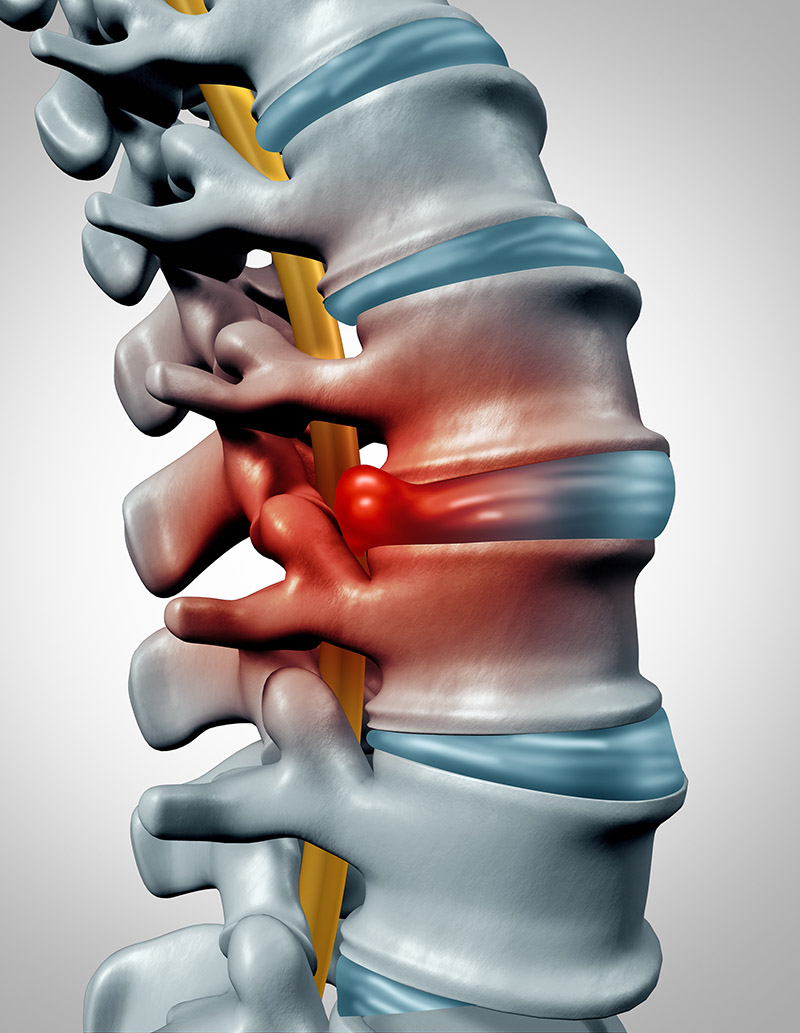

A herniated disc occurs when the soft centre of a spinal disc pushes through a crack in the tougher exterior casing. The irritation/compression of nearby nerves can lead to pain, numbness, or weakness in an arm or leg.

Among the techniques Dr. Rao uses most often in motion preservation surgery is disc replacement. This procedure involves replacing a damaged or diseased disc with an artificial one designed to mimic the function of a natural disc. It’s a sophisticated technique that reflects Dr. Rao’s commitment to innovative, patient-focused care.

During disc replacement surgery, Dr. Rao makes a small incision through which he removes the injured disc and any associated bone spurs. After the injured disc is removed, Dr. Rao then replaces it with an artificial disc designed to replicate the natural motion of the spine in that area.